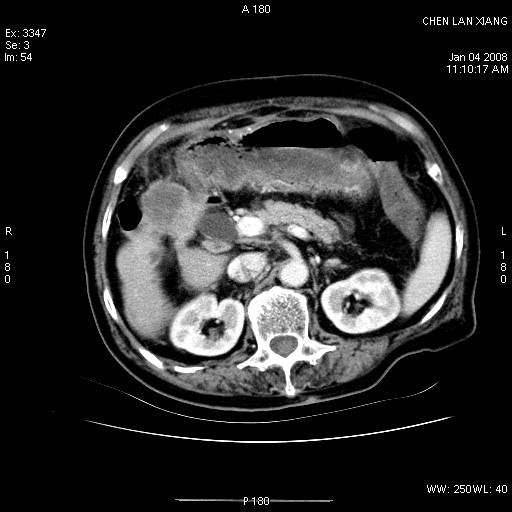

女,76岁,腹痛3-4天,b超示:肝内实性肿物,胆囊强回声,胆总管扩张.

考虑:1、胆总管下端结石伴梗阻性肝内外胆管扩张(肝左叶外侧段肝内胆管多发结石、胆管炎);

2、肿囊癌累及肝,不除外 黄色肉芽肿性胆囊炎。

1 胆总管末端结石伴肝内胆管结石,肝内外胆管扩张。2 胆囊扩大,胆囊壁不规则增厚,内见软组织密度影。考虑:慢性胆囊炎,不除外胆囊癌!

胆囊密度增高,增强后周边肝组织及胆囊窝下部周边软组织延时性不规则强化.然胆囊壁未见明显不规则增厚及肿块.左侧肝内胆管及胆总管下段结石伴胆系扩张.

考虑;胆囊炎(黄色肉芽肿性胆囊炎?),左侧肝内胆管及胆总管下段结石.

ct所见:1、 肝内胆管结石,肝内外胆管扩张。低位胆道梗阻,胆总管下端结石;2 胆囊扩大,胆囊壁不规则增厚

考虑:胆总管下端结石并肝内外胆管扩张,肝内胆管结石;

标题: 肝右叶病灶

胆囊癌侵犯肝右叶?

1)胆囊癌伴肝脏转移。2)胆总管下端结石、肝内胆管结石伴肝内外胆管扩张。